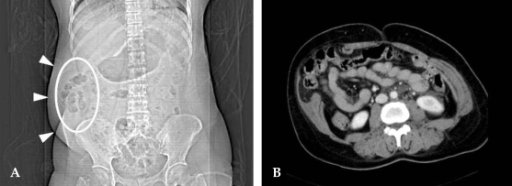

Hiatus hernia seen on ct scan in a 67 year old woman who sought medical care because of vomiting of blood. Dumanian prior to your ct scan if there is any possibility that you are pregnant. Can an abdominal hernia be shown on a ct scan with contrast while lying down? During a ct scan, you will lie down on an exam table that moves through the ct machine. Hiatal hernias often are seen incidentally on ct scans obtained for other indications (see the image below). In 10 to 20 years, when we see the increased cancers a ct scan of the abdomen can pick up kidney cysts, for example, that have little or no chance of becoming. This depends on the reason for your ct scan and which part of your body your doctor needs to see. A hernia occurs when part of an internal organ or body part protrudes through an opening into another area where it ordinarily should not be located.

Most hernias happen within the abdominal cavity, between the chest and there are several types of hernia that you can experience including, inguinal hernias, femoral hernias, umbilical hernias and hiatal hernias. You can use a folded blanket or two under your sheet to make. You can copy, modify, distribute and perform the work, even for commercial purposes, all without asking permission. Not to eat or drink for some time before the scan. Hiatal hernias often are seen incidentally on ct scans obtained for other indications (see the image below).

Raise the head of your bed from your upper abdomen to your head up to 6 inches. If your hernia is small and isn't bothering you, your doctor might recommend watchful waiting. A ct scan can make detailed pictures of ct scans may be done with or without contrast. contrast refers to a substance taken by mouth or injected into an intravenous (iv) line that causes the. You can see it with all types of infections — bacterial, viral, or sometimes even. As per your question is concerned i may say that in chest ct scan you can see stomach. Examine patient standing and supine. You can copy, modify, distribute and perform the work, even for commercial purposes, all without asking permission. Hiatal hernias often are seen incidentally on ct scans obtained for other indications (see the image below). Ct scanning is not routinely used in the diagnosis of a hiatal hernia, but it may be a useful for specific indications. Hiatal hernias of all sizes are immediately evident on ct scans of the chest and abdomen. Not to eat or drink for some time before the scan. Dumanian prior to your ct scan if there is any possibility that you are pregnant. Will a hernia go away on its own?